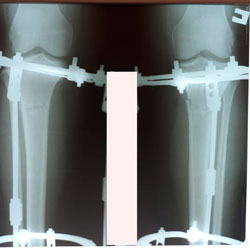

Исходник - 49 лет.

Дата операции - 11.02.2021

image-08-04-21-12-43-5.jpg

image-08-04-21-12-43-2.jpg